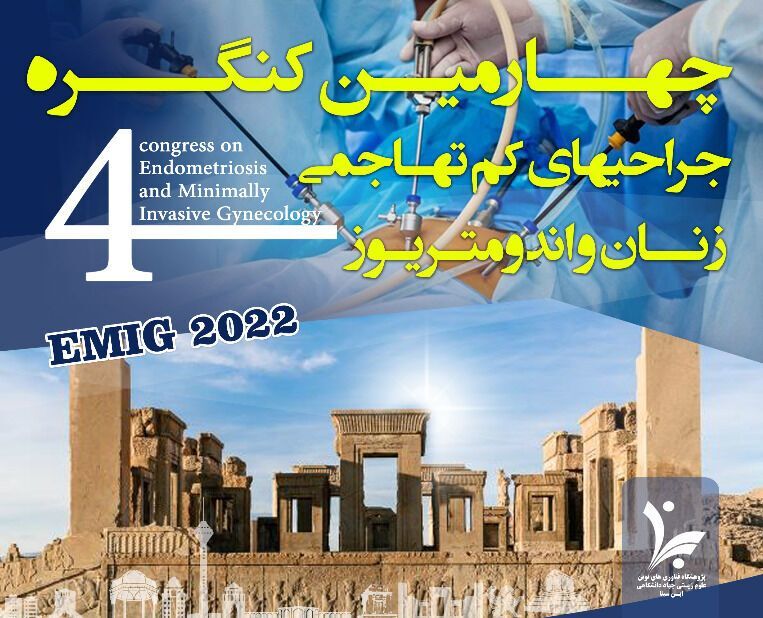

تهران- ایرنا- متخصصان و جراحان نامدار ایران و جهان در چهارمین کنگره جراحیهای کمتهاجمی زنان و اندومتریوز که روزهای ۷، ۸، ۱۴ و ۱۵ بهمن...